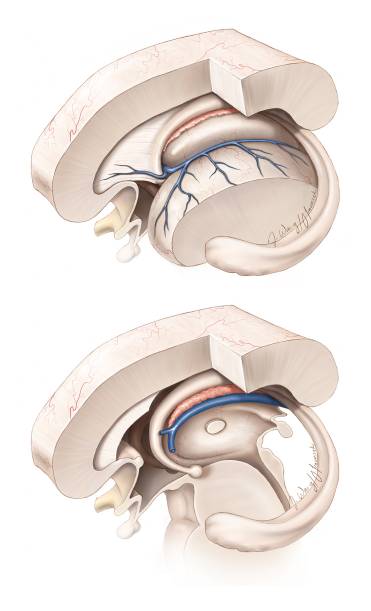

图7. 图示脉络丛、透明隔静脉和丘纹静脉的手术解剖。通过脉络膜裂前部一小段分离扩大室间孔的关键操作是在隔静脉汇入丘纹静脉之前切断。穹隆和丘纹静脉必须被保留。尽管笔者更愿意沿丘脑侧分离脉络裂而不是沿穹隆一侧分离来达到保护穹隆的目的,但是脉络裂的实际解剖更可能提示最合理的分离界面。换句话来讲,笔者并不推荐固定的分离策略(总是沿着丘脑脉络带或者穹隆带)。穹隆构成室间孔前壁的边界,在器械移动过程中应该注意保护。

图8. 图示经室间孔经静脉经脉络膜入路的术中视野角度(绿色区域)和视角盲点(红色区域)。